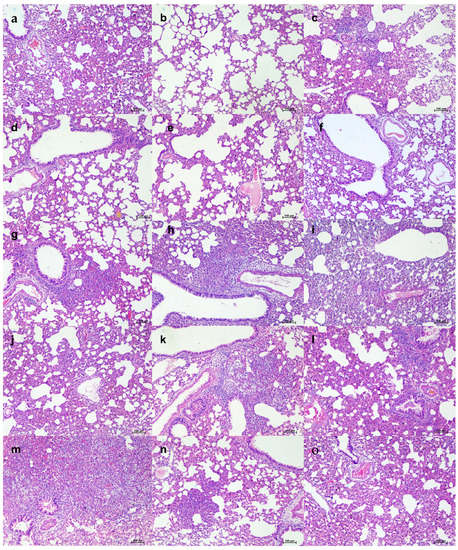

We studied the therapeutic potential with 105.5 TCID50 (high virus dose) at 24 h (Figure 6a) and 6 h post challenge and with 103.5 TCID50 (low) virus dose at 24 h after infection. In the 105.5 TCID50-challenged (at 24 h) group, no significant difference could be observed with body weight loss among groups, whereas gain in body weight was observed in the 50 mg/kg group (Figure 6b). The mAb levels in the serum remained constant from Day 3 to Day 7 without much drop (Supplementary Table S2). Although gRNA and sgRNA levels in the respiratory tract showed a decreasing trend in all the groups until 7DPI, there was no statistical significance in comparison to control in the viral load (Figure 6c–g). Grossly pneumonic changes were observed in all groups with comparable lung weights to that of placebo group. On histopathological examination, moderate to severe pneumonic changes were observed in all treated and control groups (Figure 6h, Supplementary Figure S2).

Figure 6.

mAb therapy at 24 h post high virus dose challenge in hamsters. (a) Study design, (b) percent bodyweight gain in hamsters on 3 (n = 12/group), 5 (n = 8/group), and 7 (n = 4/group) DPI. Viral genomic RNA load (n = 4/group) in (c) nasal wash, (d) nasal turbinates, and (e) lungs post infection. Viral sub genomic RNA load in hamsters’ (f) nasal turbinates and (g) lungs post infection. (h) Cumulative score of lung pathological changes in hamsters (n = 3/group) post virus challenge. Mean ± SD is plotted on the graph, and a comparison was performed between the treated groups and the control groups. A Kruskal–Wallis test followed by Mann–Whitney test was used to assess statistical significance. An asterisk indicates a significant difference between the means, with * representing p < 0.05, respectively, and the dotted line on the graph indicates the assay limit of detection.

Further, we performed therapeutic evaluation of the mAb cocktail (50 and 5 mg/kg) at 6 h post virus (105.5 TCID50) infection to understand the ability of mAb to neutralize at a shorter interval treatment (Figure 7a). The body weight reduction was observed in both the treated groups (Figure 7b). Although the placebo group showed considerably higher body weight loss than the mAb-treated groups, it was not statistically significant. The average gRNA load in nasal wash, nasal turbinate, and lungs on 3 and 5 DPI did not show any significant difference among groups (Figure 7c–e). SgRNA levels showed reduction in comparison to the placebo group and were completely cleared from nasal turbinates and lungs by 5 DPI in all mAb-treated groups (Figure 7f,g). On histopathological examination, mild changes were seen in the 50 mg/kg dose group, whereas the hamsters of the 5 mg/kg group showed to mild to moderate changes, and the placebo group showed moderate pneumonic changes (Figure 7h, Supplementary Figure S3).

Figure 7.

mAb therapy at 6 h following high virus dose challenge in hamsters. (a) Study design, (b) percent bodyweight gain/loss in hamsters on 3 (n = 6/group) and 5 (n = 3/group) post SARS-CoV-2 infection. Viral gRNA load (n = 3/group) in (c) nasal wash, (d) nasal turbinates, and (e) lungs in hamsters post virus challenge. Viral sgRNA load (n = 3/group) in (f) nasal turbinates and (g) lungs in hamsters post virus challenge. (h) Cumulative histopathological score of lung pathological changes in hamsters (n = 3/group) on 3 and 5 DPI. Mean ± SD is plotted on the graph, and a comparison was performed between the treated groups and the control groups. A Kruskal–Wallis test followed by a Mann–Whitney test was used to assess statistical significance. The dotted line on the graph indicates the assay detection limit.